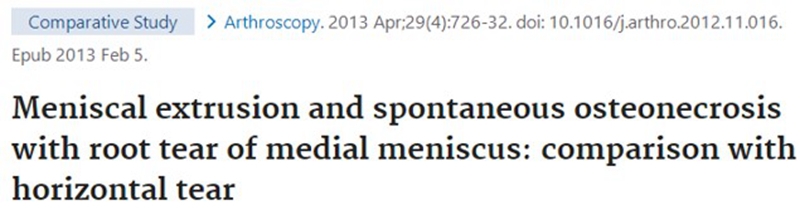

SONK与内侧半月板后根部损伤,有国外学者在SONK患者中通过MRI及关节镜检查,常可发现合并内侧半月板后根部的撕裂,该发生率可达到80%(24/30), 15例完全撕裂,9例部分撕裂。结果表明SONK可能与内侧半月板后根部撕裂后,导致股骨负重区的应力集中、软骨下骨髓水肿有关。

SONK与内侧半月板突出的相关研究中,100%(104)SONK中都有半月板突出,4个SONK在发病前因膝关节疼痛体检发现半月板突出,几个月后通过MRI检查显示存在 SONK。

研究证明半月板挤压是SONK的发病机制之一,半月板挤压的进展可能与SONK的发展有关。